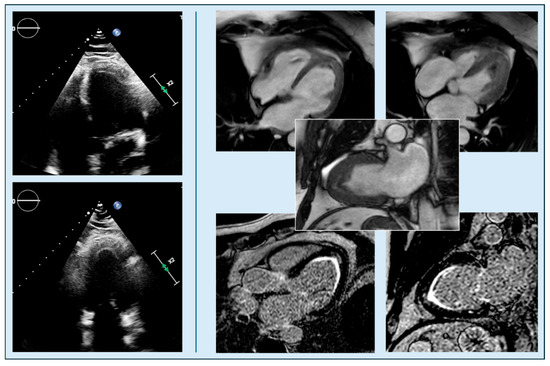

The use of non-invasive imaging techniques is undeniably one of the aspects that best characterize modern cardiology. With the implementation of percutaneous interventional procedures in the treatment of structural heart disease, and current advances in the management of chronic ischemic heart disease, metabolic storage diseases, and heart failure in clinical practice, imaging methods are required to provide increasingly sophisticated evaluation parameters, in order to adopt adequate therapeutic strategies and identify the patients best suited to undergo certain procedures. Therefore, clinicians in cardiac patient management cannot ignore the power of the complete and precise information provided by non-invasive diagnostic methods such as echocardiography, cardiac magnetic resonance imaging, cardiac CT, and nuclear cardiology, which can greatly facilitate correct diagnosis and adequate prognostic stratification.